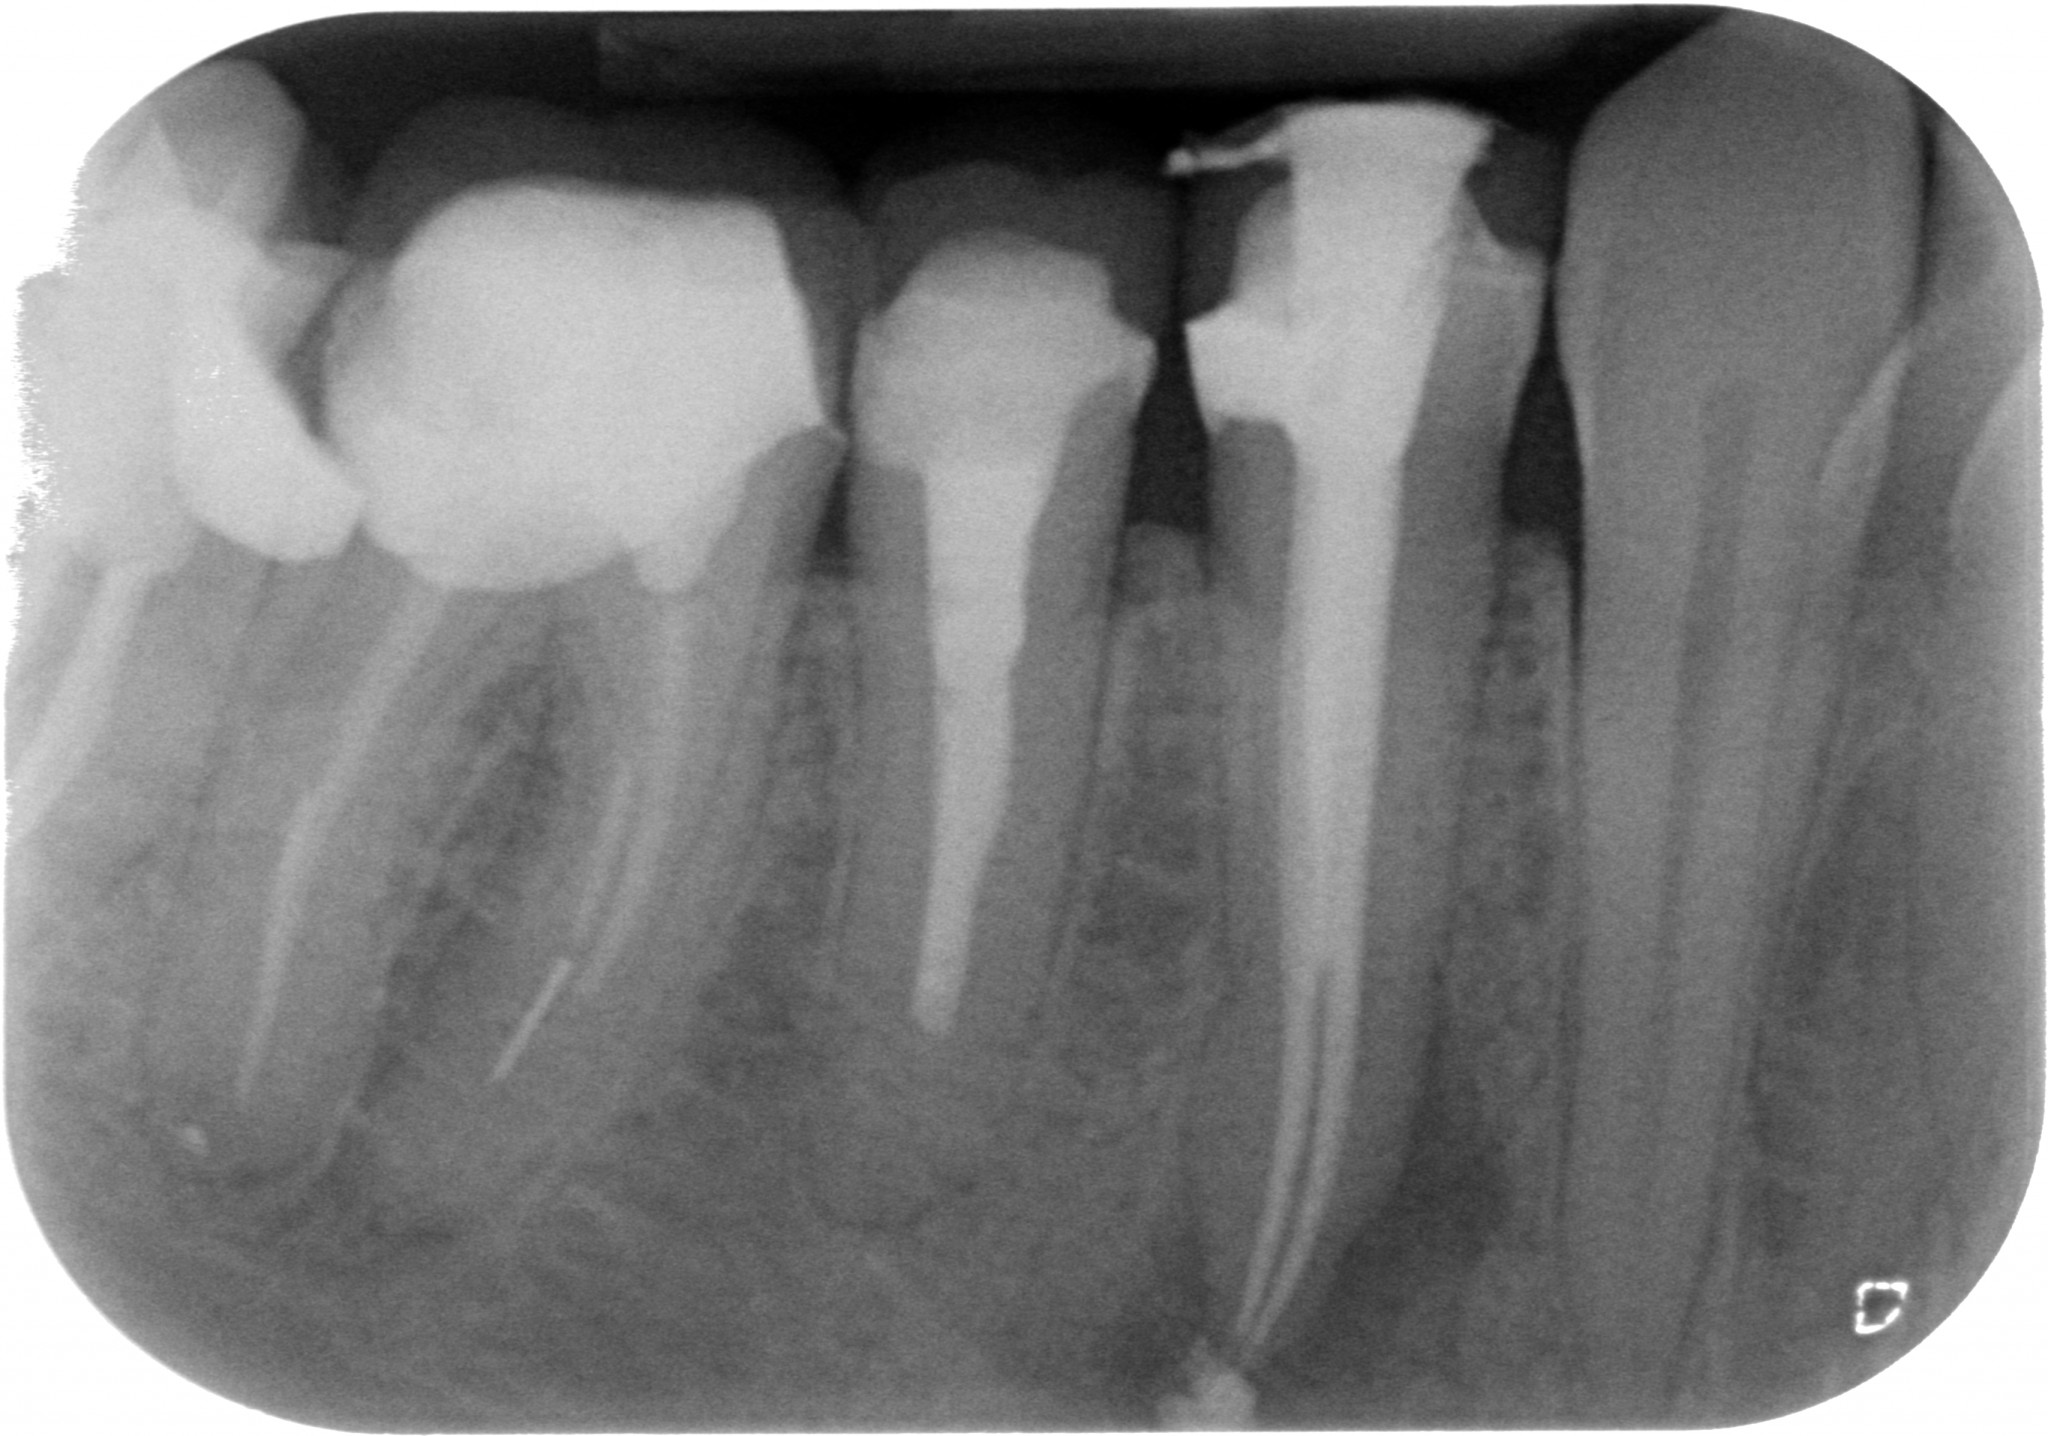

E sai com’è…io i perni dopo il Thermafil, dopo aver capito come fare, li mettevo…e non mi veniva via il carrier e i perni non si staccavano…all’inizio raffreddavo la gutta col crio spray, poi ho capito che basta condensarla con un plugger, prima di tagliare il carrier con una Post space bur della Dentsply…anche se so che questo non è possibile, per cui il carrier ricrescerà o mi si staccheranno tutti i perni da qui a qualche mese…Vedere un post space completamente deterso come questo è sicuramente un inganno…

E arrivandomi il microscopio ho cominciato a trovare anatomie assurde a josa…E le riuscivo a chiudere solo coi thermafil…anche se in realtà evidentemente credevo solo di farlo, perché era impossibile. Guarda questo primo premolare inferiore che ho ritrattato un mesetto fa…forcazione a 5 mm dal fondo del dente…in pratica una IV classe di Weine…Secondo te con cosa l’ho chiuso? ?

Thermafil - Anatomia difficile iniziale Thermafil - Anatomia difficile lunghezze Thermafil - Anatomia difficile finale